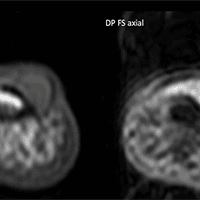

Paciente do sexo feminino, 47 anos, com lesão nodular dolorosa subungueal no I dedo há meses. Relata aumento da sensibilidade nesta região, especialmente no frio.

Imagens